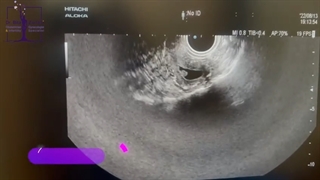

فیبروم های رحمی در بارداری